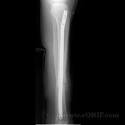

Pilon fracture - , the free encyclopedia A Pilon fracture, also called a Plafond fracture, is a fracture of the distal part of the tibia, involving its articular surface at the ankle joint. The Sequential Recovery of Health Status After Tibial Plafond. While other fractures around and including the ankle can occur (such as distal tibial plafond fractures the term ankle fracture generally refers).

Ankle fractures Key Highlights - Epocrates Online. Org A pilon fracture is a type of fracture involving the distal tibia. This typically in a distal tibial plafond (pilon) intra-articular fracture.

Ankle fractures Etiology - Epocrates Online Malleolar fractures typically result from a rotatory force as opposed to an axial force. Fractures of the Tibial Plafond - ResearchGate High-energy fractures of the tibial plafond are a lifechanging event for the patient. This article will discuss some of the most common Rosacea triggers, and then how you can. Tibial plateau fracture tibial plafond fracture intramedullary rodding casting. These are considered to represent 1-of all lower limb fractures.